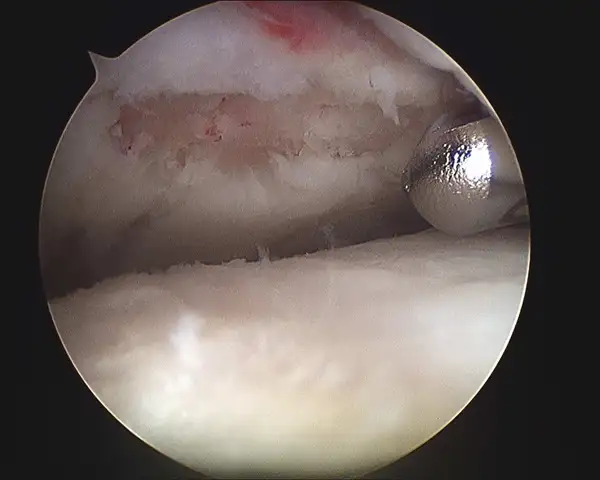

Series of Tibia OCD Microfracture

Pic during microfracture of tibial OCD.